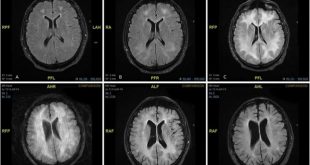

- استفاده از داروهای مختلف با هم همبستگی دارد. ساختار ارتباطی در شکل بالا ارائه شده است.